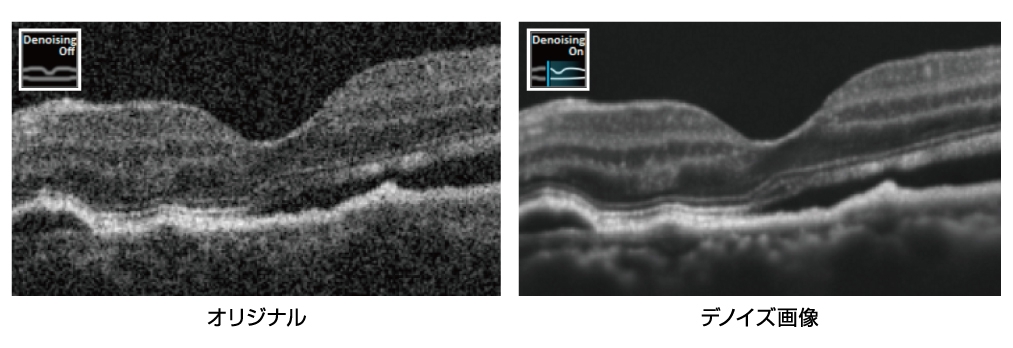

- Bスキャンデノイジングソフトウェアを搭載可能(オプション)

HD8スキャン

HD8スキャンは、高コントラスト・低ノイズの画像が取得できます。

スキャン数は、HD2スキャン、HD4スキャン、HD8スキャンが選択できます。

同範囲で撮影をした場合、HD8スキャンの方がより鮮明に画像を取得することができます。